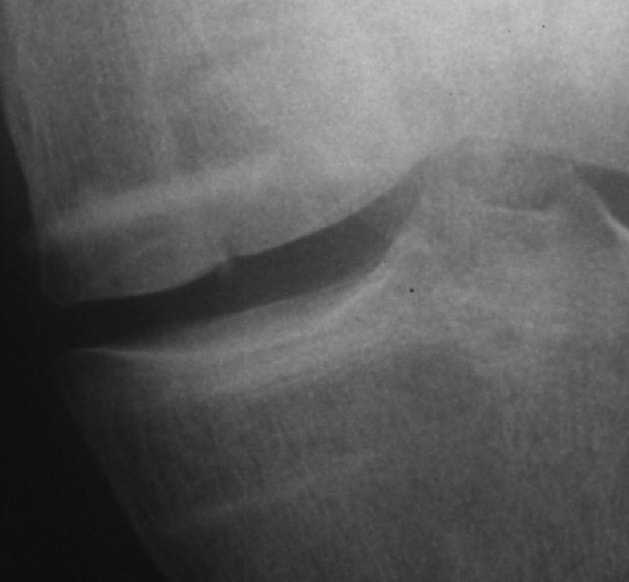

6 Monate postoperativ

Röntgenkontrolle seitlich. Transplantat ist eingewachsen.